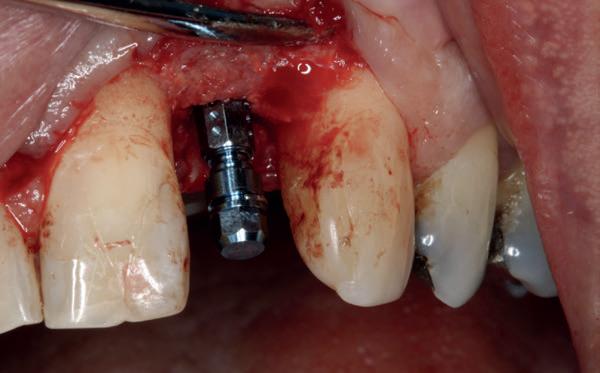

Op 16-jarige leeftijd werd de patiënt door haar behandelend orthodontist naar de auteur verwezen voor een restauratieve oplossing voor de afwezige 11 en 21. In de tussenliggende periode had patiënt een retainer gedragen met twee kunststof tanden (afbeelding 1). Zowel de patiënt als haar moeder hadden een sterke voorkeur voor een implantaat gedragen vaste oplossing. Gezien haar jonge leeftijd was dit echter nog geen optie, omdat er nog verticale groei te verwachten viel. Implanteren op jonge leeftijd – dat wil zeggen vóór het 21e levensjaar – kan resulteren in een infrapositie van het implantaat, omdat de rest van het gebit nog verticaal kan doorgroeien.

Middels shared decision making werd het volgende plan overeengekomen: eerst zou er een etsbrug met vleugels op de 12 en 22 worden vervaardigd, om op 21-jarige leeftijd verder te gaan met implantologie.

Bij klinisch en röntgenologisch onderzoek viel echter op dat radix van de 12 en 22 een convergerende (de radices staan dan naar mesiaal en naar elkaar toe) in plaats van divergerende (radices staan dan van elkaar af) stand had. Door deze convergerende stand van de radices was er in mesio-distale zin geen ruimte voor twee implantaten ter plaatse van de 11 en 21. Er werd daarom besloten, in tegenzin

1. Retainer met twee frontelementen

2. OPT radices 12 en 22 convergeren

3. Vaste apparatuur voor torque 12 en 22

4. OPT radices 12 en 22 divergeren na orthodontische behandeling

van de patiënt, om eerst weer vaste apparatuur terug te plaatsen om de radices in een divergerende stand te plaatsen. Gelukkig verliep deze behandeling voorspoedig. (afbeelding 2 -4). Het volgende behandelplan werd gemaakt: